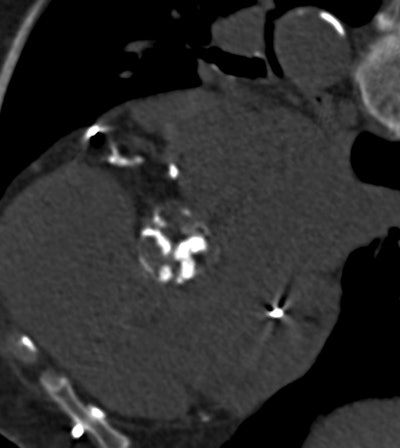

The researchers performed noncontrast CT using multidetector scanners from Siemens Healthcare (Somatom Sensation) or Philips Healthcare (Mx8000 IDT 16). Aortic valve calcium measurements were performed on an offline workstation using HeartBeat CS (Philips) or Aquarius iNtuition (TeraRecon). Results were calculated using the Agatston calcium scoring method, with results expressed in arbitrary units (AU).

Based on previous echocardiography research by the authors, aortic valve calcium values of at least 1,274 AU in women and 2,065 AU in men were set as the optimal cutoff for defining severe AVC. To account for variability in body size, a second measure indexing AVC to the cross-sectional area of the aortic annulus was used, with AVCdensity thresholds of 292 AU/cm2 for women and 476 AU/cm2 for men.

Coronary calcifications, visible in the CT scans and also measured, were considered severe when they were greater than the median value in the patient population, the authors noted. Echocardiography and CT were performed within nine days of each other. The primary study end point was overall survival under medical treatment, while secondary end points included cardiovascular death under medical management and survival during the entire follow-up period, regardless of AVI status.